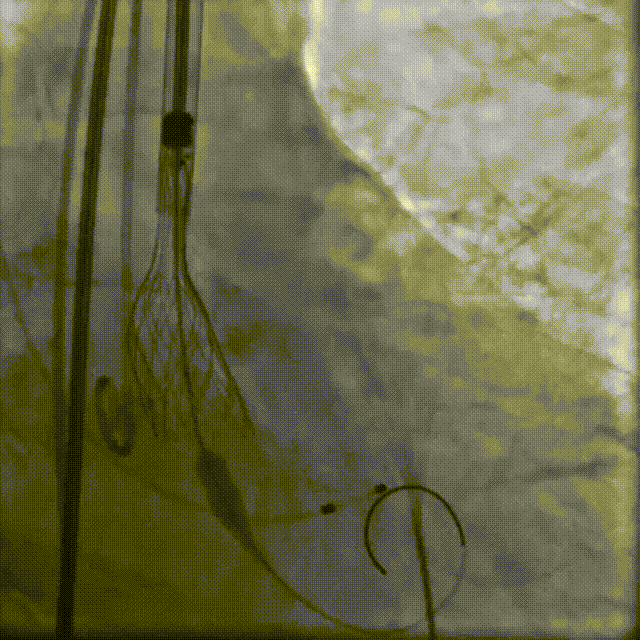

TaurusElite AV26瓣膜轻松过弓跨瓣,瓣膜初始定位瓣环0位,120bpm起搏下精准释放,释放到工作位后造影显示锚定充足,位置良好,冠脉未见遮挡,继续完成释放。

瓣膜初始定位

瓣膜释放过程

瓣膜释放后造影观察,根据影像判断反流较多,选择23mm球囊进行后扩。球囊后扩后反流量减少,瓣膜形态佳。

瓣膜脱钩